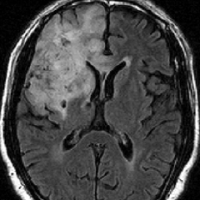

症候性てんかんのみで発症した右側頭葉と島回のグレード2オリゴです。左のT2,中央のフレアではグレード2びまん性星細胞腫と鑑別はできません。認知機能などは正常でした。

何と言っても診断的価値があるのは 石灰化 carcification です。左のCTの中央にみえる白い部分が石灰化です。この程度の石灰化でも診断的な価値があります。1p/19q codeletionがあるオリゴでした。病理では,均一な小型の円形核を有する細胞と多数の毛細血管 chickin-wire network がみられます。部分摘出後,放射線治療とテモゾロマイド化学療法でコントロールできています。